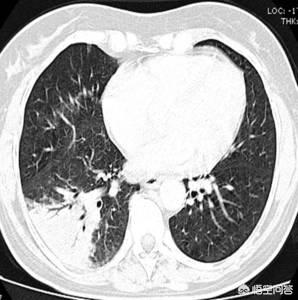

所谓肺炎型肺癌,并非一个病理学属于,而是指在影像学上表现为斑片状、大片状实变或磨玻璃样阴影,跟肺炎非常相似,但其病理基础却是肺癌的一个约定成俗,已经逐渐被淘汰的概念。

(肺腺癌)

通过上面两幅图,可以看出来,这种表现为斑片状影的肺癌,跟肺炎在CT上非常相似。